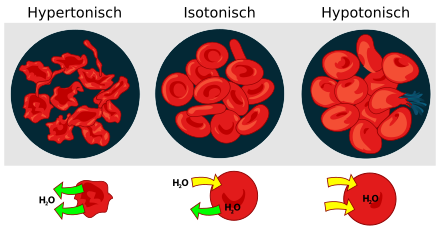

Osmoregulation

Wird die osmotische Resistenz roter Blutkörperchen durch Einbringen in destilliertes Wasser (stark hypotones Medium) überschritten, nehmen sie unkontrolliert Wasser auf, bis sie schließlich platzen. Ihre Zellmembranen können nur einem geringeren Druck standhalten. Pflanzenzellen dagegen sind von einer stützenden Zellwand umgeben, wodurch sie erheblich höhere Innendrücke (→ Turgor) aushalten.

In der Medizin wird für Infusionen eine isotonische Kochsalzlösung eingesetzt, um eine Schädigung der Körperzellen durch osmotischen Druck zu vermeiden. Es handelt sich dabei um ein Gemisch aus Wasser mit 0,9 % (Massenprozent) Kochsalz, die Osmolarität dieser Lösung entspricht mit 308 mosmol/l annähernd der des Blutplasmas, dies entspricht einem osmotischen Druck von 0,7 MPascal. Würde bei Infusionen reines Wasser anstatt einer isotonen Lösung benutzt werden, könnte ein solcher Druckunterschied die Blutzellen platzen lassen.